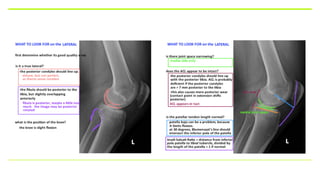

• STANDING XRAY OF KNEE AP AND LATERAL VIEW

SCANNOGRAMANDPATELLA